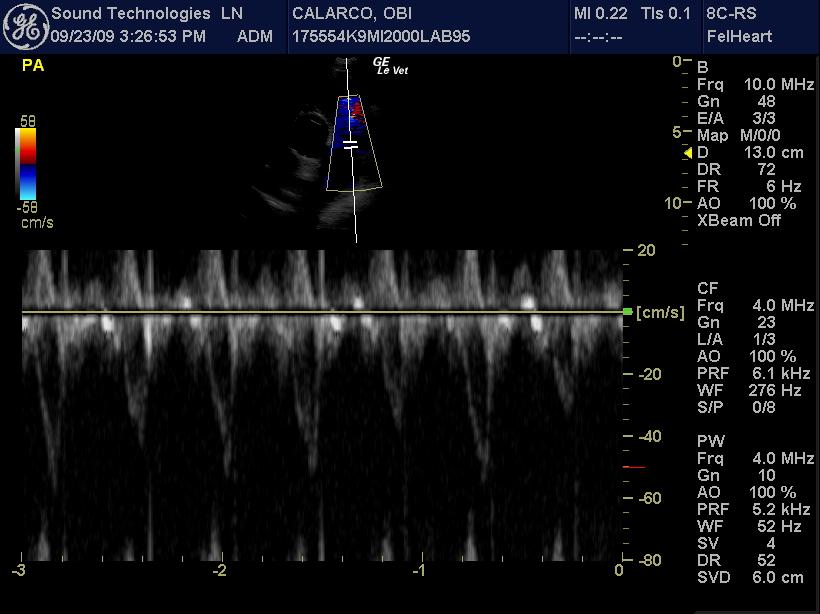

An 11-year-old MN Labrador retriever was prestented for excercise intolerance, lethargy, depression, vomiting and diarrhea. The physical exam was unremarkable other than a grade 2 left sided heart mumur at the heart base and irregular heart beat with pulse deficits. CBC, CHEM, UA, and acth stim were all normal.